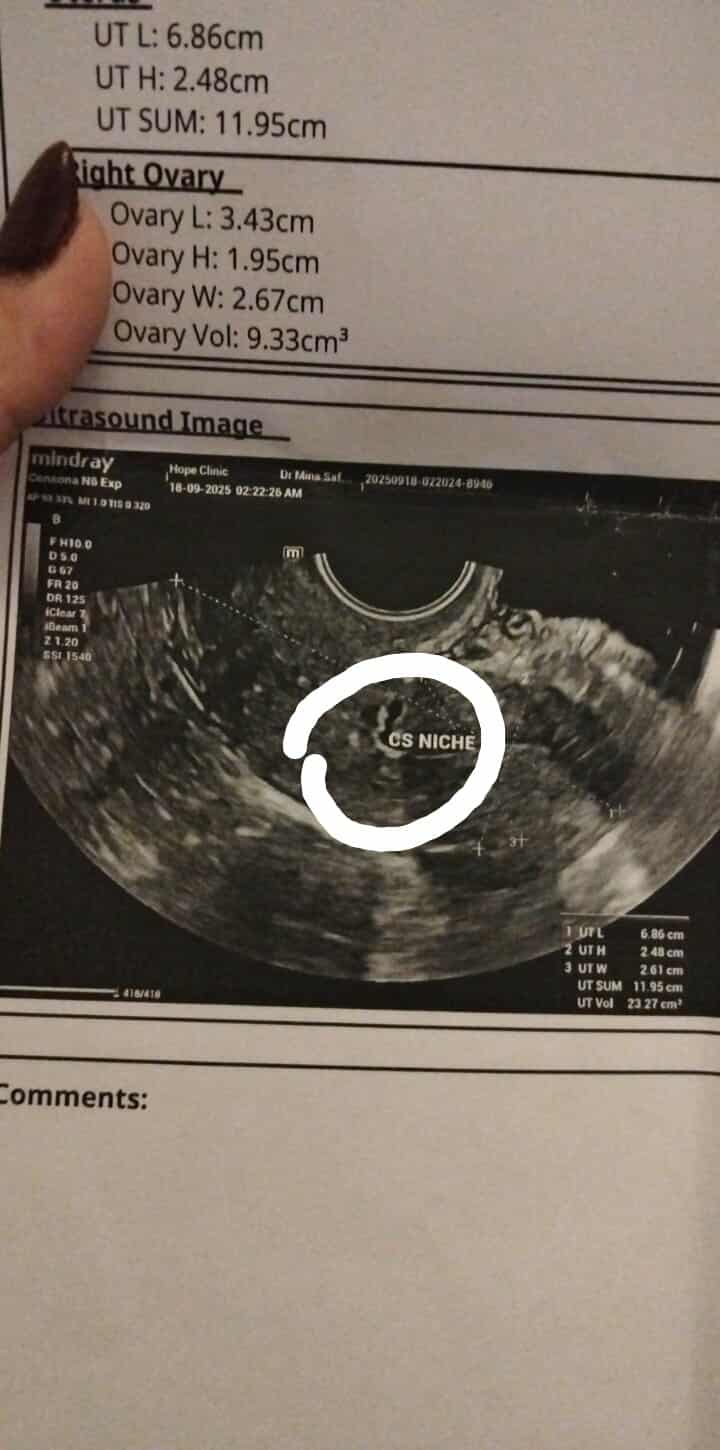

هل الجراب اللي ف جرح القيصريه يمنع الحمل